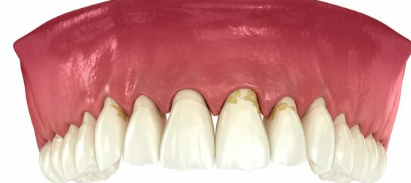

4. 잇몸이 내려가고 치아가 길어 보인다 – 잇몸 퇴축 현상

잇몸뼈가 녹아내리면, 잇몸이 치아뿌리 쪽으로 물러나면서 치아가 길어 보이는 현상이 나타납니다.

- 거울로 보면 치아가 평소보다 길게 보임

- 잇몸 경계가 울퉁불퉁하고 균일하지 않음

- 찬물 마실 때 시림이 심해짐

▶ 치아가 길어지는 건 단순한 미용 문제가 아닌 치아지지 구조 약화의 증거입니다.